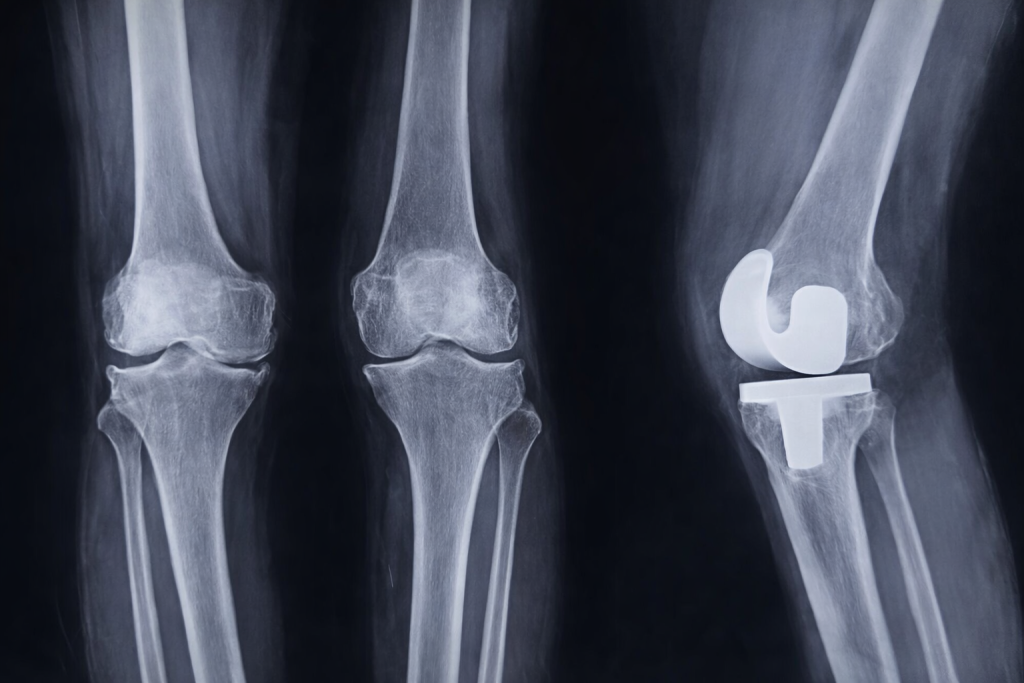

- X-ray showing joint damage

What is Total Knee Replacement Surgery?

In Total Knee Replacement (TKR), the damaged knee joint is removed and replaced with an artificial implant made of medical-grade metal and plastic. This new joint: